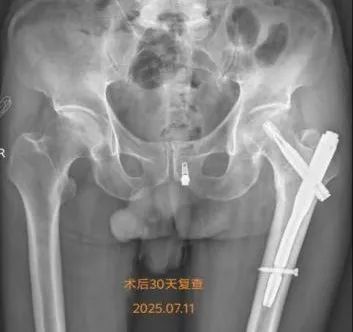

在何流教授的指导下,骨外科主治医师王亮利用C臂机精准引导通过31-2厘米的小切口完成骨折复位与固定手术50分钟,过程顺利,术中出血量仅50毫升

术后,还对戴爷爷进行了康复早期介入。术后第一天,开展了踝关节屈伸训练第三天,借助翻身枕进行侧卧位交替,有效预防压疮形成。

戴爷爷在我院多学科医护人员的精心治疗下,仅用1个月就实现了从卧床不起到借助助行器行走的跨越。